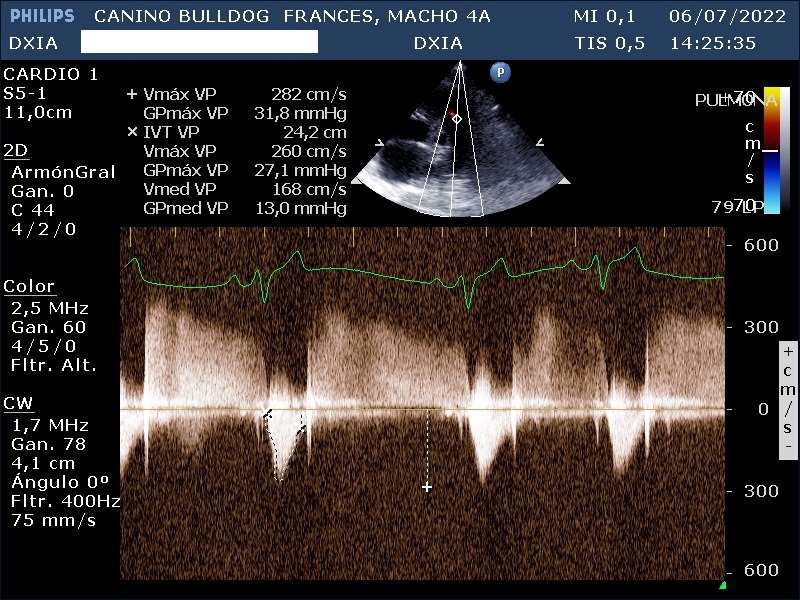

- Válvula tricúspide: Normoimplantada. Valva parietal más alargada que la valva septal. Flujo regurgitante leve-moderado de Vmáx RT: 348 cm/s y GPmáx RT: 48,5 mmHg.

- Válvula pulmonar: Normoimplantada. Estenosis pulmonar leve con una velocidad de 271mmHg. Insuficiencia con una velocidad diastólica de 74,8 mmHg.